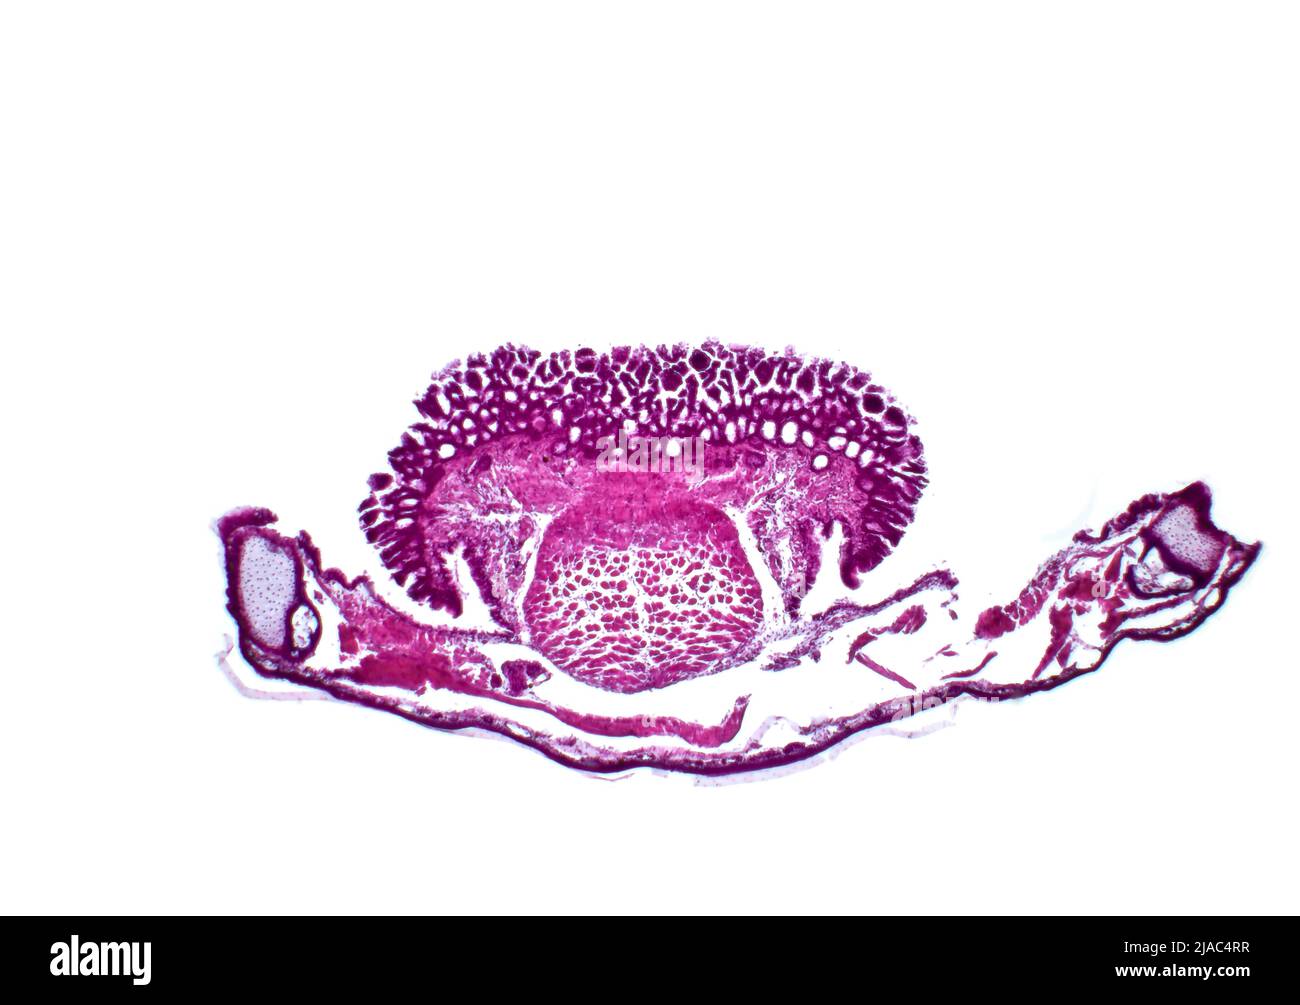

Langue et mâchoire inférieure d'une grenouille (Pélophylax ridibundus), microscopie optique. Coloration à l'hématoxyline et à l'éosine. Banque D'Imageshttps://www.alamyimages.fr/image-license-details/?v=1https://www.alamyimages.fr/langue-et-machoire-inferieure-d-une-grenouille-pelophylax-ridibundus-microscopie-optique-coloration-a-l-hematoxyline-et-a-l-eosine-image471093723.html

Langue et mâchoire inférieure d'une grenouille (Pélophylax ridibundus), microscopie optique. Coloration à l'hématoxyline et à l'éosine. Banque D'Imageshttps://www.alamyimages.fr/image-license-details/?v=1https://www.alamyimages.fr/langue-et-machoire-inferieure-d-une-grenouille-pelophylax-ridibundus-microscopie-optique-coloration-a-l-hematoxyline-et-a-l-eosine-image471093723.htmlRF2JAC4RR–Langue et mâchoire inférieure d'une grenouille (Pélophylax ridibundus), microscopie optique. Coloration à l'hématoxyline et à l'éosine.